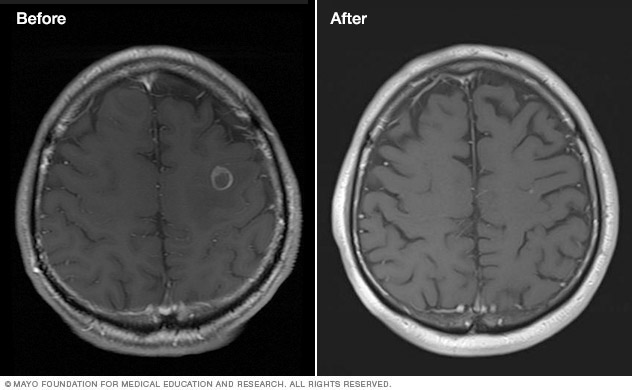

Stereotactic Radiosurgery Middlesex Health